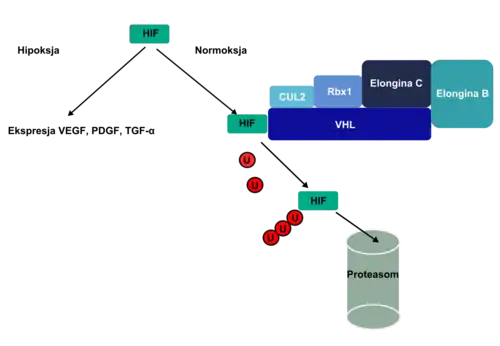

El producto de la proteína clara del gen VHL tiene una longitud de 213 aminoácidos y su funcionamiento se relaciona con la proteína clara elongina-B y elongina-C. Esta relación en el complejo VHL-elongina B-elongina C mantiene la ligazón entre las proteínas claras especificadas y es la base de su ubicuitinación (el complejo tiene un nivel de estructura proteínica E3). Se afirmó que los sustratos del complejo VBC son las proteínas claras HIF1α y HIF2α, junto a la proteína clara atípica λ (de kinaza??); cuando esta ligadura tiene lugar se establece la proteína clara domena β VHL; por ello la proteínas claras quedan sujeta a ubicuitinación y determinadas por la misma, degradándose a proteasomas.